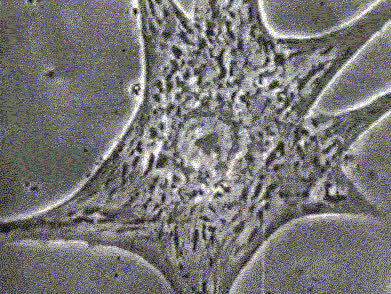

10、细胞有丝分裂

上皮细胞通过有丝分裂可将每条染色体精确复制成两条染色单体并均等分到两个子细胞中,使子细胞含有同母细胞相同的遗传信息。